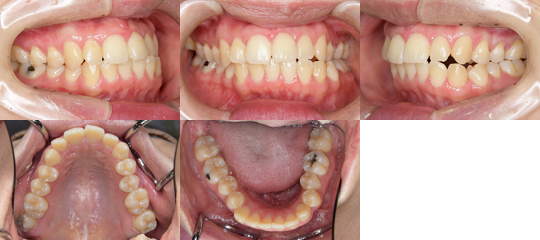

下記に、顎矯正手術を施行した顎変形症(顔面非対称)の症例の初診時の

口腔内写真を示しています。

右側臼歯部の鋏状咬合と上顎咬合平面の右下がり傾斜を伴う顔面非対称

(Le Fort T型骨切り術+下顎枝垂直骨切り術)

上顎咬合平面の左上がり傾斜と下顎骨左方偏位を呈する顔面非対称(Le Fort T型骨切り術+下顎枝垂直骨切り術) 初診時

詳しい治療経過をご覧になられる場合は画像をクリックして下さい。